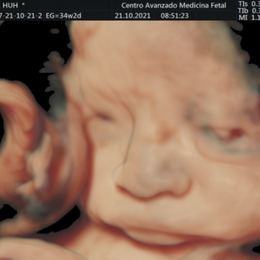

En un embarazo normal o de bajo riesgo se recomienda realizarse tres ecografías, una por trimestre. La primera entre las semanas 11 y 14, la segunda entre la 18 y la 22 y la tercera entre la 32 y la 36. Descubre para qué sirve cada una de ellas.